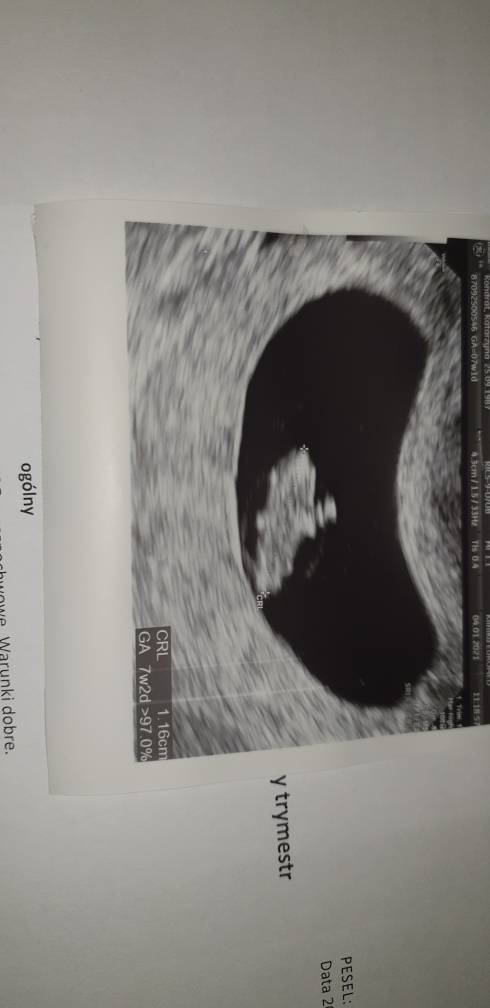

Ja już jestem po wizycie u swojej gin. Wszystko jest w porządku, maluch rośnie dziś mierzył 1,16 mm jest to 7+1 termin z OM idealnie pokrywa się z tym z usg termin porodu wyznaczony na 22.08. Kolejna wizyta dopiero 15.02 od razu będę miała usg prenatalne. A co do plamień to ustały i przyczyny nie widać, dalej mam brać luteinę do 13 tyg ciąży zapobiegawczo. Moja gin mówiła, że czasami taka uroda i plamienia się zdarzają i nie muszą oznaczać nic złego.

20210104_155445.jpeg

Załączniki

• 20210104_151406.jpeg

20210104_151406.jpeg

26,1 KB · Wyświetleń: 84